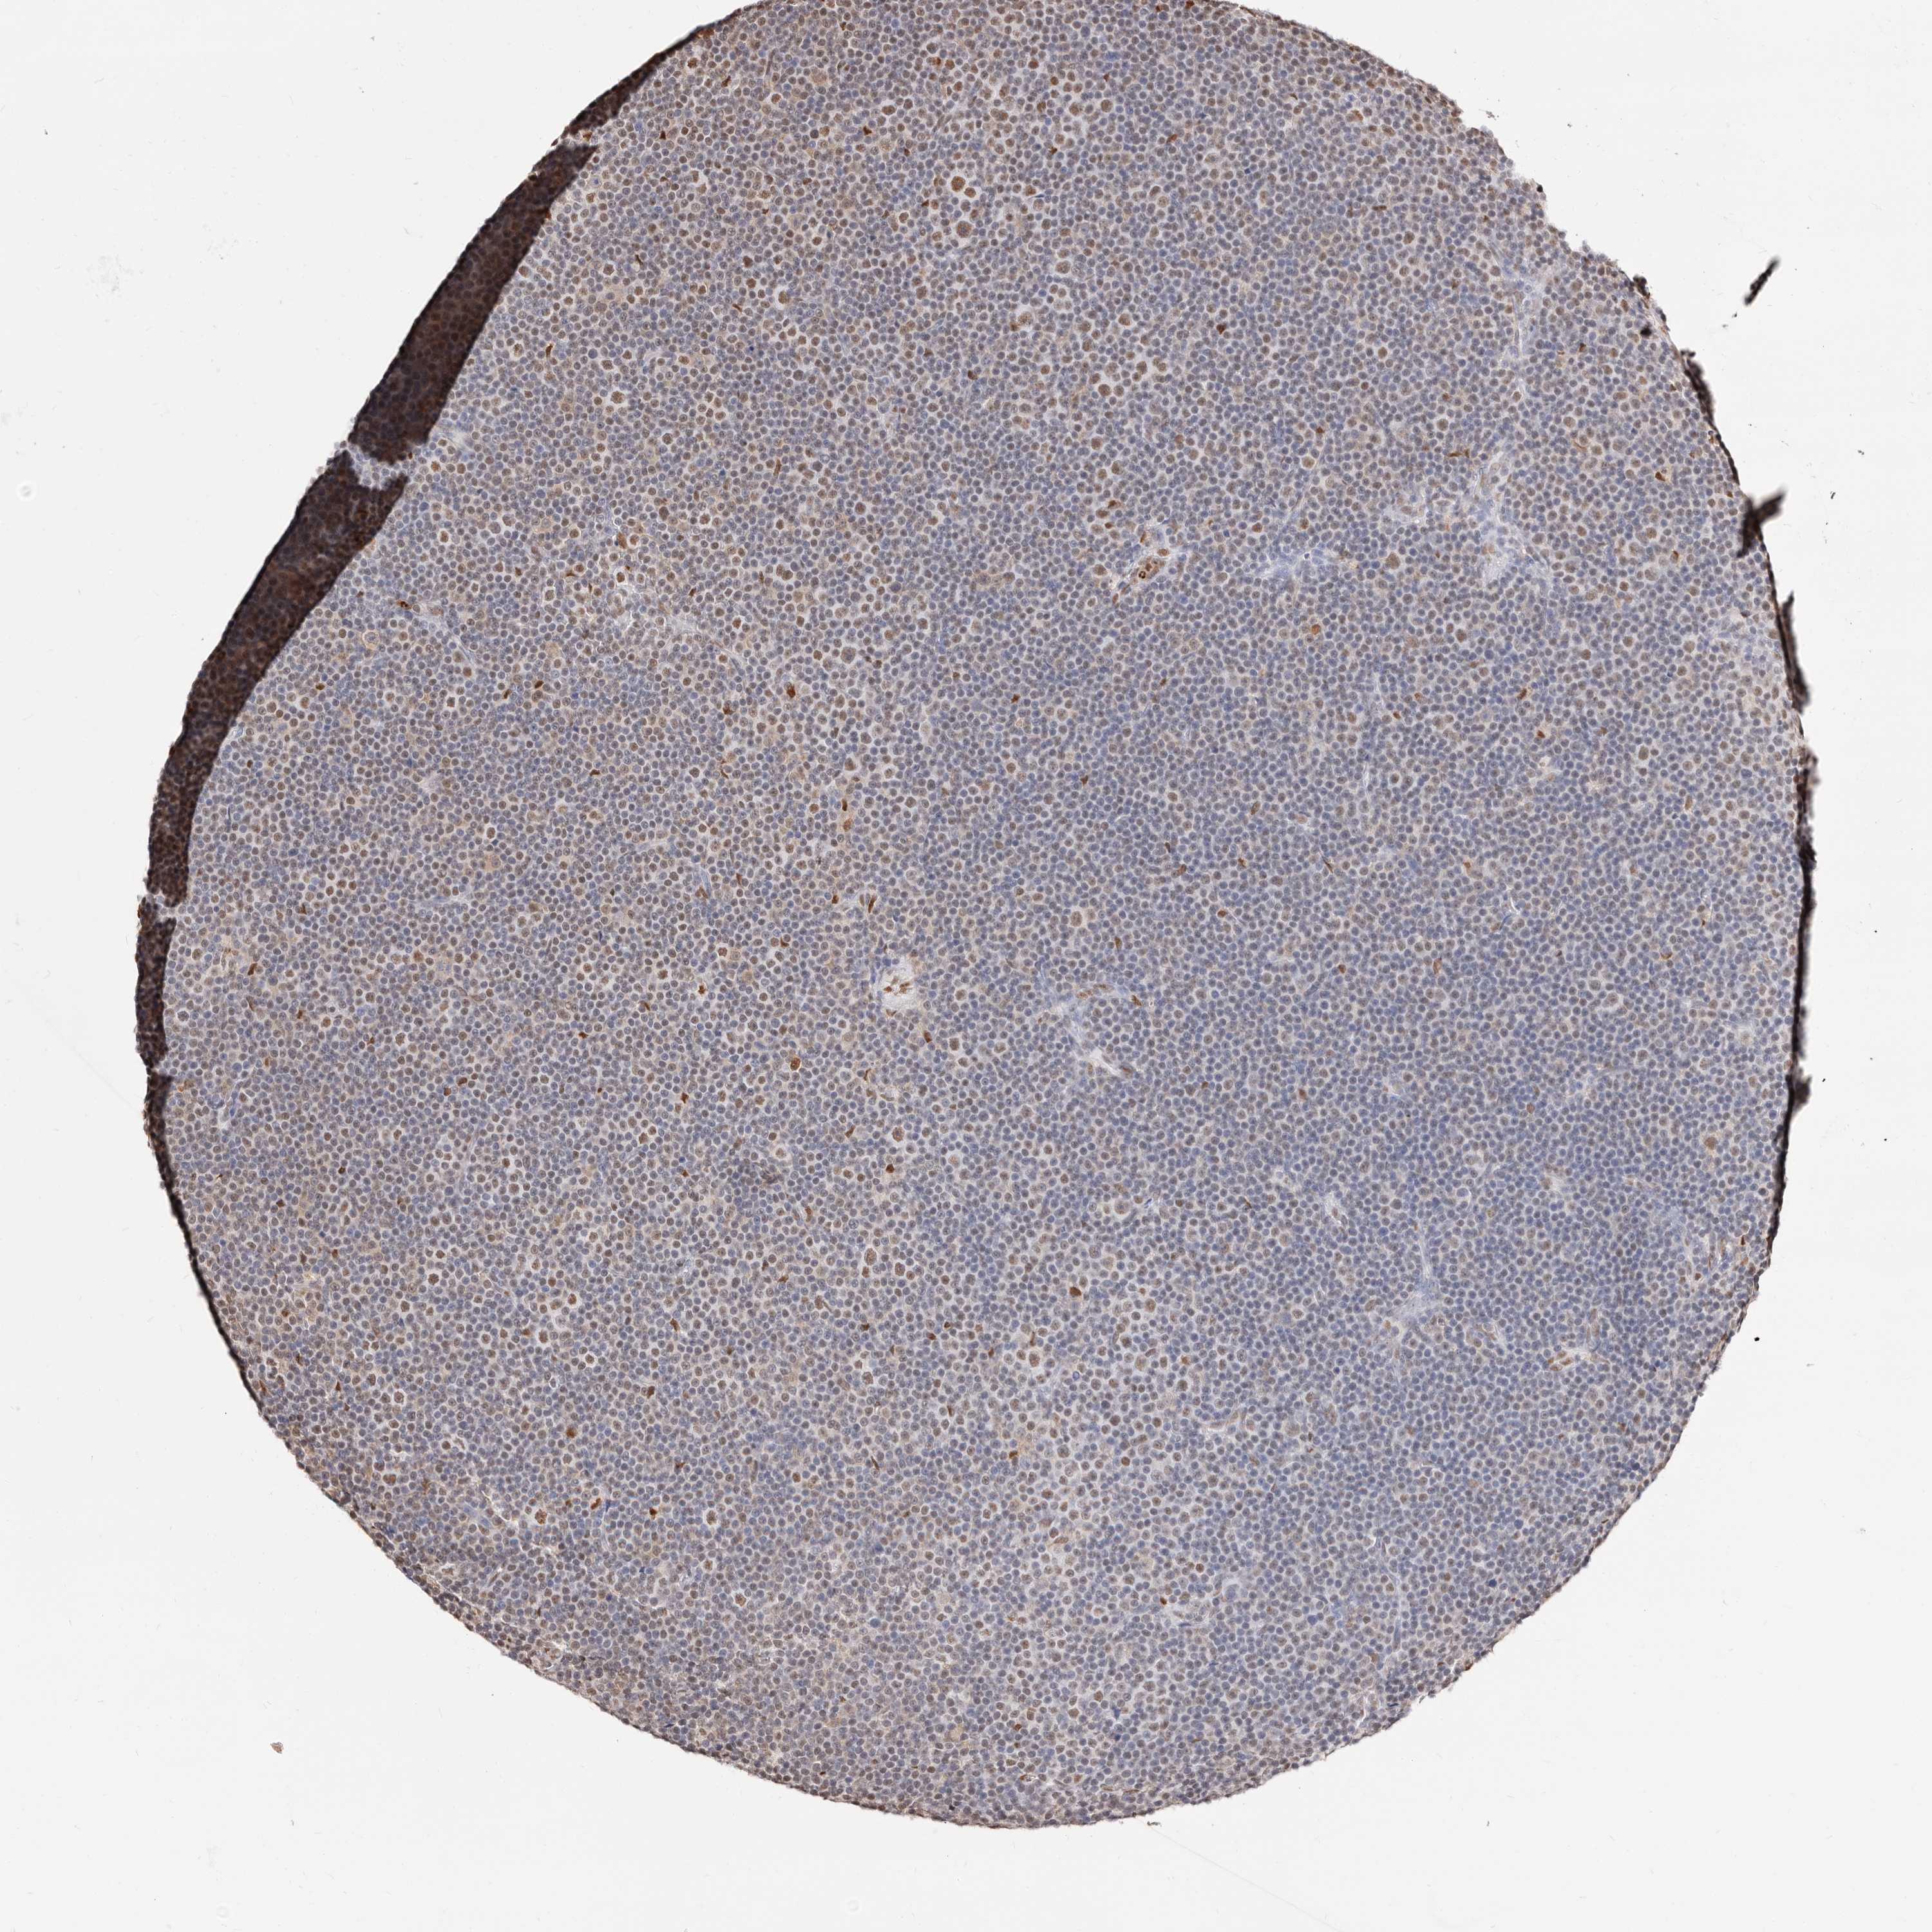

LYMPHOMA - Protein expressioni

A mouse-over function shows sample information and annotation data. Click on an image to view it in a full screen mode. Samples can be filtered based on level of antibody staining by selecting one or several of the following categories: high, medium, low and not detected. The assay and annotation is described here.

Antibody stainingi

Antibody staining in the annotated cell types in the current human tissue is reported as not detected, low, medium, or high, based on conventional immunohistochemistry profiling in selected tissues. This score is based on the combination of the staining intensity and fraction of stained cells.

Each image is clickable and will lead to virtual microscopy that enables deeper exploration of all samples and also displays staining intensity scores, fraction scores and subcellular localization as well as patient and tissue information for each sample.

Antibody HPA029480

Intensity

Strong

Moderate

Weak

Negative

Quantity

>75%

75%-25%

<25%

None

Location

Nuclear

Cytoplasmic/membranous

Cytoplasmic/membranous,nuclear